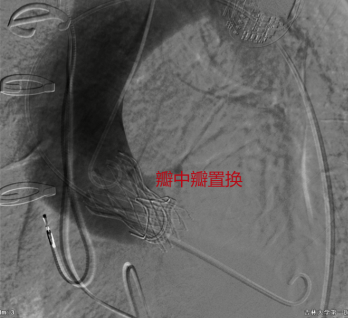

8月16日,吉大一院心臟外科TAVR手術團隊為一名開胸瓣膜置換術后復發并伴有心力衰竭患者實施微創介入“瓣中瓣”手術,在此前置換的失功生物瓣膜內部成功植入新瓣膜,為患者再造“心門”。該手術為吉林省首例經導管主動脈瓣“瓣中瓣”置換術,填補了吉林省該領域治療空白。

8月9日,心臟外科主任馬大實統籌,教授高永生主刀,醫生楊立明、劉宇帥輔助,在麻醉科、第二手術室、超聲診斷中心—心臟超聲科等科室的密切配合下,為患者實施經導管主動脈瓣“瓣中瓣”置換術?;颊咝g后主動脈瓣貼合良好,無返流、無瓣周漏,憋悶胸痛癥狀明顯改善,心功能逐漸恢復正常,術后第4日順利康復出院。